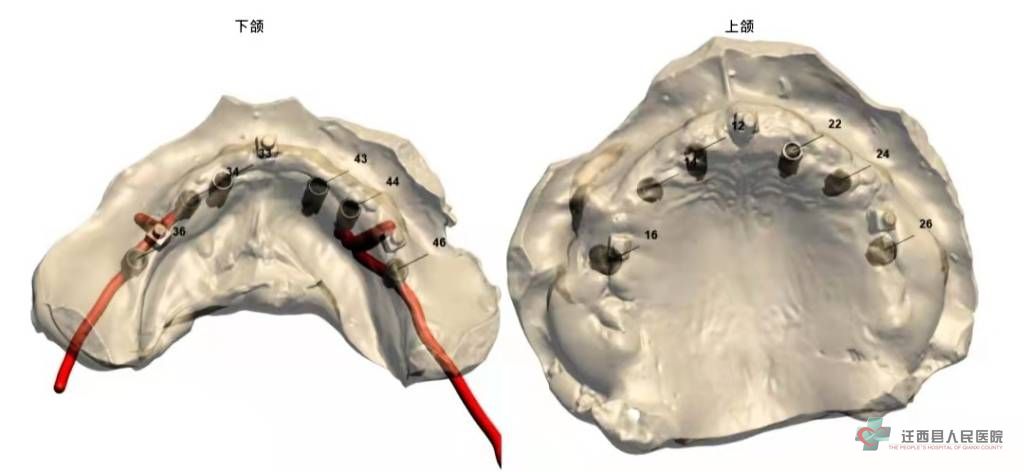

种植前计算机导板设计